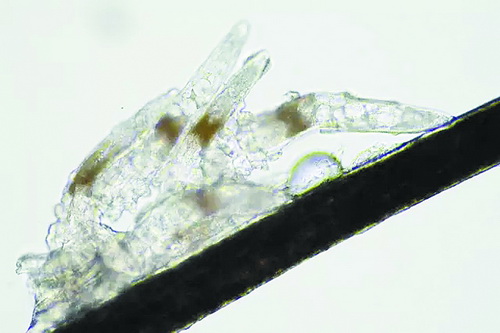

顯微鏡下長在睫毛中的螨蟲

冬天來了,氣溫降低,睫毛上的“隱形殺手”蠕形螨卻沒有要冬眠的意思。廈門大學(xué)附屬廈門眼科中心11月初開設(shè)蠕蟲性瞼緣炎門診以來,每天來查螨的市民都特別多,短短一個多月,已有近千人在顯微鏡下見到長期寄居在自己睫毛上,朝夕相處,卻素未謀面的蠕形螨。

蠕形螨怎么就跑進(jìn)眼睛里了呢?原來,蠕形螨以吃角質(zhì)蛋白、油脂為生,而我們的睫毛和瞼板腺等地方油脂分泌旺盛,正是螨蟲寄居的理想場所。蠕形螨有兩種,一種是寄生在睫毛、眉毛毛囊里的毛囊蠕形螨,一種是寄生在皮脂腺和瞼板腺內(nèi)的皮脂蠕形螨,它們在眼睛里吸食油脂、吞噬上皮細(xì)胞、產(chǎn)卵、排泄,會引發(fā)一系列不良反應(yīng)。